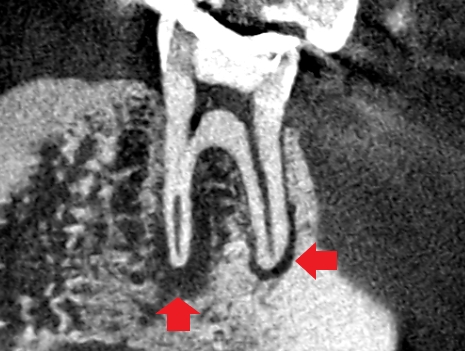

精密根管治療6ヶ月後の経過観察時の冠状断のCT画像です。青い矢印の先にあった膿の影が縮小し歯槽骨が再生してきています。